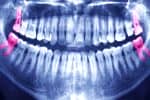

Los expertos dicen que en las últimas décadas, la caries se ha vuelto muy joven. Hoy en día, la formación de manchas en los dientes de los niños ya no es algo sorprendente. Todos los padres se preguntan si es necesario tratar tales problemas o si simplemente se puede quitar un diente malo para siempre.

Dado que el esmalte de los niños es mucho menos duro que el esmalte de los adultos, las enfermedades se desarrollan mucho más rápido. Por ejemplo, incluso una caries pequeña en solo dos o tres semanas puede convertirse en un agujero profundo y doloroso. Tal lesión está cargada con el desarrollo de pulpitis y otras dolencias desagradables.

El estado de la cavidad oral en el futuro y la salud de las unidades indígenas dependen en gran medida del cuidado adecuado de los dientes de leche y su correcto desarrollo. Si se extraen los primeros dientes, pueden aparecer los siguientes problemas:

- Crecimiento incorrecto de las constantes. De hecho, en la encía debajo de los primeros dientes ya hay futuros molares, y la extracción demasiado temprana puede provocar violaciones del desarrollo posterior.

- Puede aparecer maloclusión. Después de la extracción, queda un espacio vacío en el lugar del diente anterior, que los dientes sanos restantes tienden a ocupar. Como resultado, puede comenzar un crecimiento caótico, el desarrollo de la mandíbula puede verse afectado y ralentizado. Todo esto puede causar el desarrollo de maloclusión en un bebé, cuya corrección requiere mucho tiempo y costos financieros.